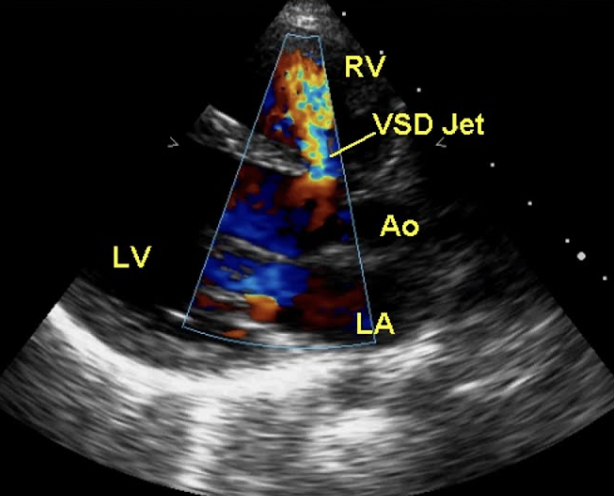

19

Q

What kind of VSD is this?

A

Perimembranous

20

What is this? Be specific

Perimembranous VSD

21

What is this?